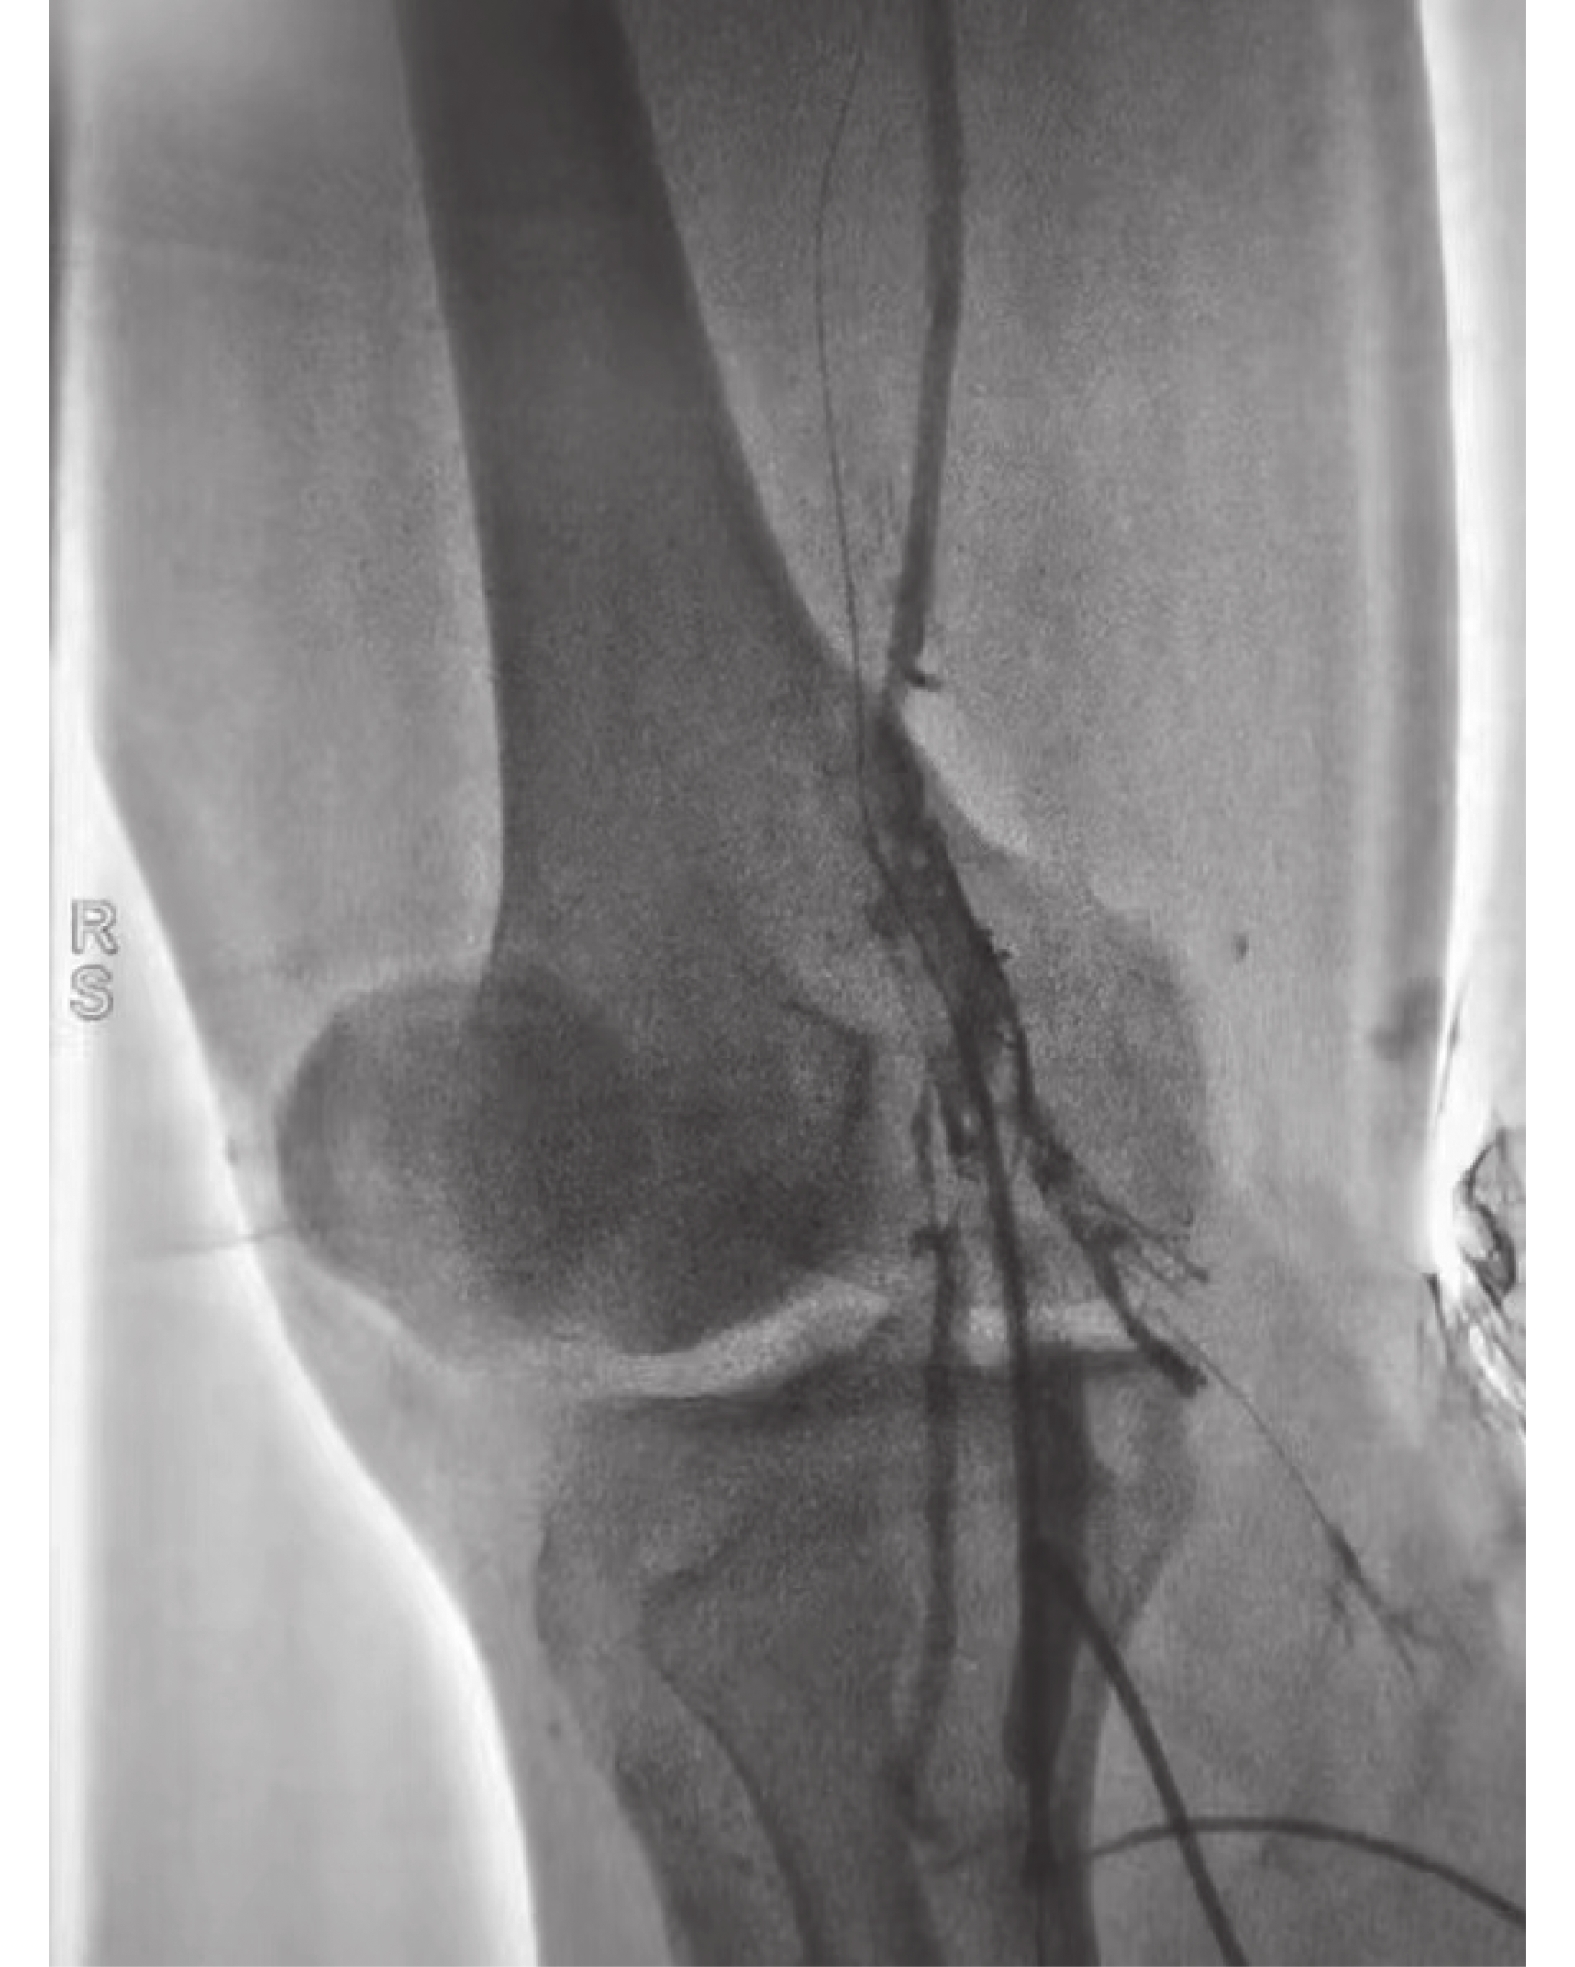

Correlation between Esophageal Manometry and Short-term Efficacy of Endoscopic Myotomy in Patients with Achalasia

Yingye SONG, Juanping LI, Rui LI

2026, 47(4): 147-154. doi: 10.12259/j.issn.2095-610X.S20260418

Abstract:

Objective  To investigate the correlation between esophageal manometry and short-term efficacy of peroral endoscopic myotomy in patients with achalasia of cardia (AC).   Methods  Clinical data of AC patients who underwent POEM treatment for the first time in the Department of Gastroenterology at The First Affiliated Hospital of Soochow University from January 2019 to September 2024 were selected and grouped based on the 2020 Chicago 4.0 and Ling classifications. Baseline data and surgical response rates of the patients were analyzed so as to compare Eckardt scores and esophageal manometry data of patients in different groups and the correlation between esophageal manometry data and postoperative clinical efficacy were analysed.   Results  (1)The surgical success rate of 272 patients included in this study was 100%. The preoperative Eckardt score was (6.65 ± 1.48) points, and the Eckardt score 3 months after the surgery was (1.05 ± 0.56) points. The Eckardt score after POEM surgery decreased significantly compared to preoperative levels, and the difference was statistically significant (t = 19.823, P < 0.001). The postoperative Eckardt scores of the three groups of patients classified by Chicago and the five groups of patients classified by Ling were significantly lower than those before the surgery, and the differences were statistically significant (P < 0.05). (2) The postoperative LESP and 4SIRP of the three groups of patients classified by Chicago were significantly reduced compared with preoperative levels, and the differences were statistically significant (P < 0.05). And there was a statistically significant difference in the postoperative LESP and 4SIRP among the three groups of patients (P < 0.05). Further comparison using Bonferroni method showed that the LESP and 4SIRP of Group II were lower than those of Group I and Group III (P < 0.05), but there was no statistically significant difference between Group I and Group III (P > 0.05). The postoperative LESP and 4SIRP of the five groups of patients classified by Ling were also lower than those before the surgery, and the comparison was statistically significant (P < 0.05). There was also a statistically significant difference (P < 0.05) in the postoperative LESP and 4SIRP among the five groups of patients. Further comparison using Bonferroni method showed that the LESP and 4SIRP of groups IIa, IIb, IIc, and III were significantly lower than those of group I (P < 0.05), but there was no statistically significant difference between groups IIa, IIb, IIc, and III (P > 0.05). (3) The severity of 4SIRP and Eckardt scores showed a moderate correlation (r = 0.428, P = 0.001); The severity of LESP and Eckardt scores showed a mild correlation (r = 0.245, P = 0.004).   Conclusion  The short-term clinical efficacy of POEM treatment for AC is significant, with Chicago type II AC patients showing the best response to POEM treatment. Ling’ s classification of type IIa, IIb, IIc, and III shows better efficacy than type I. Moreover, there is a moderate correlation between the 4SIRP and Eckardt scores in the HRM parameters, which has good evaluation value for the postoperative efficacy of POEM.